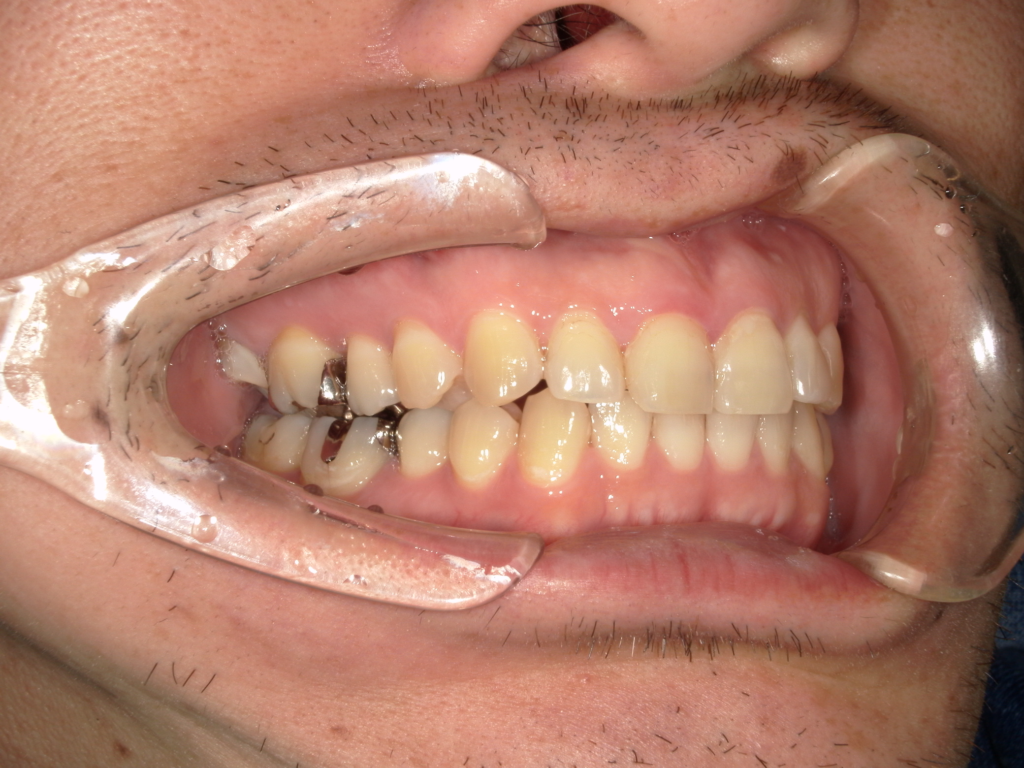

Y様インプラント実例 #44

左の上下の奥歯をインプラントで治療しています。

左下の奥歯は歯を抜くのと同時にインプラントの埋め込みを行っています。

被せものは上下、セラミックスで作っています。

治療前

治療後